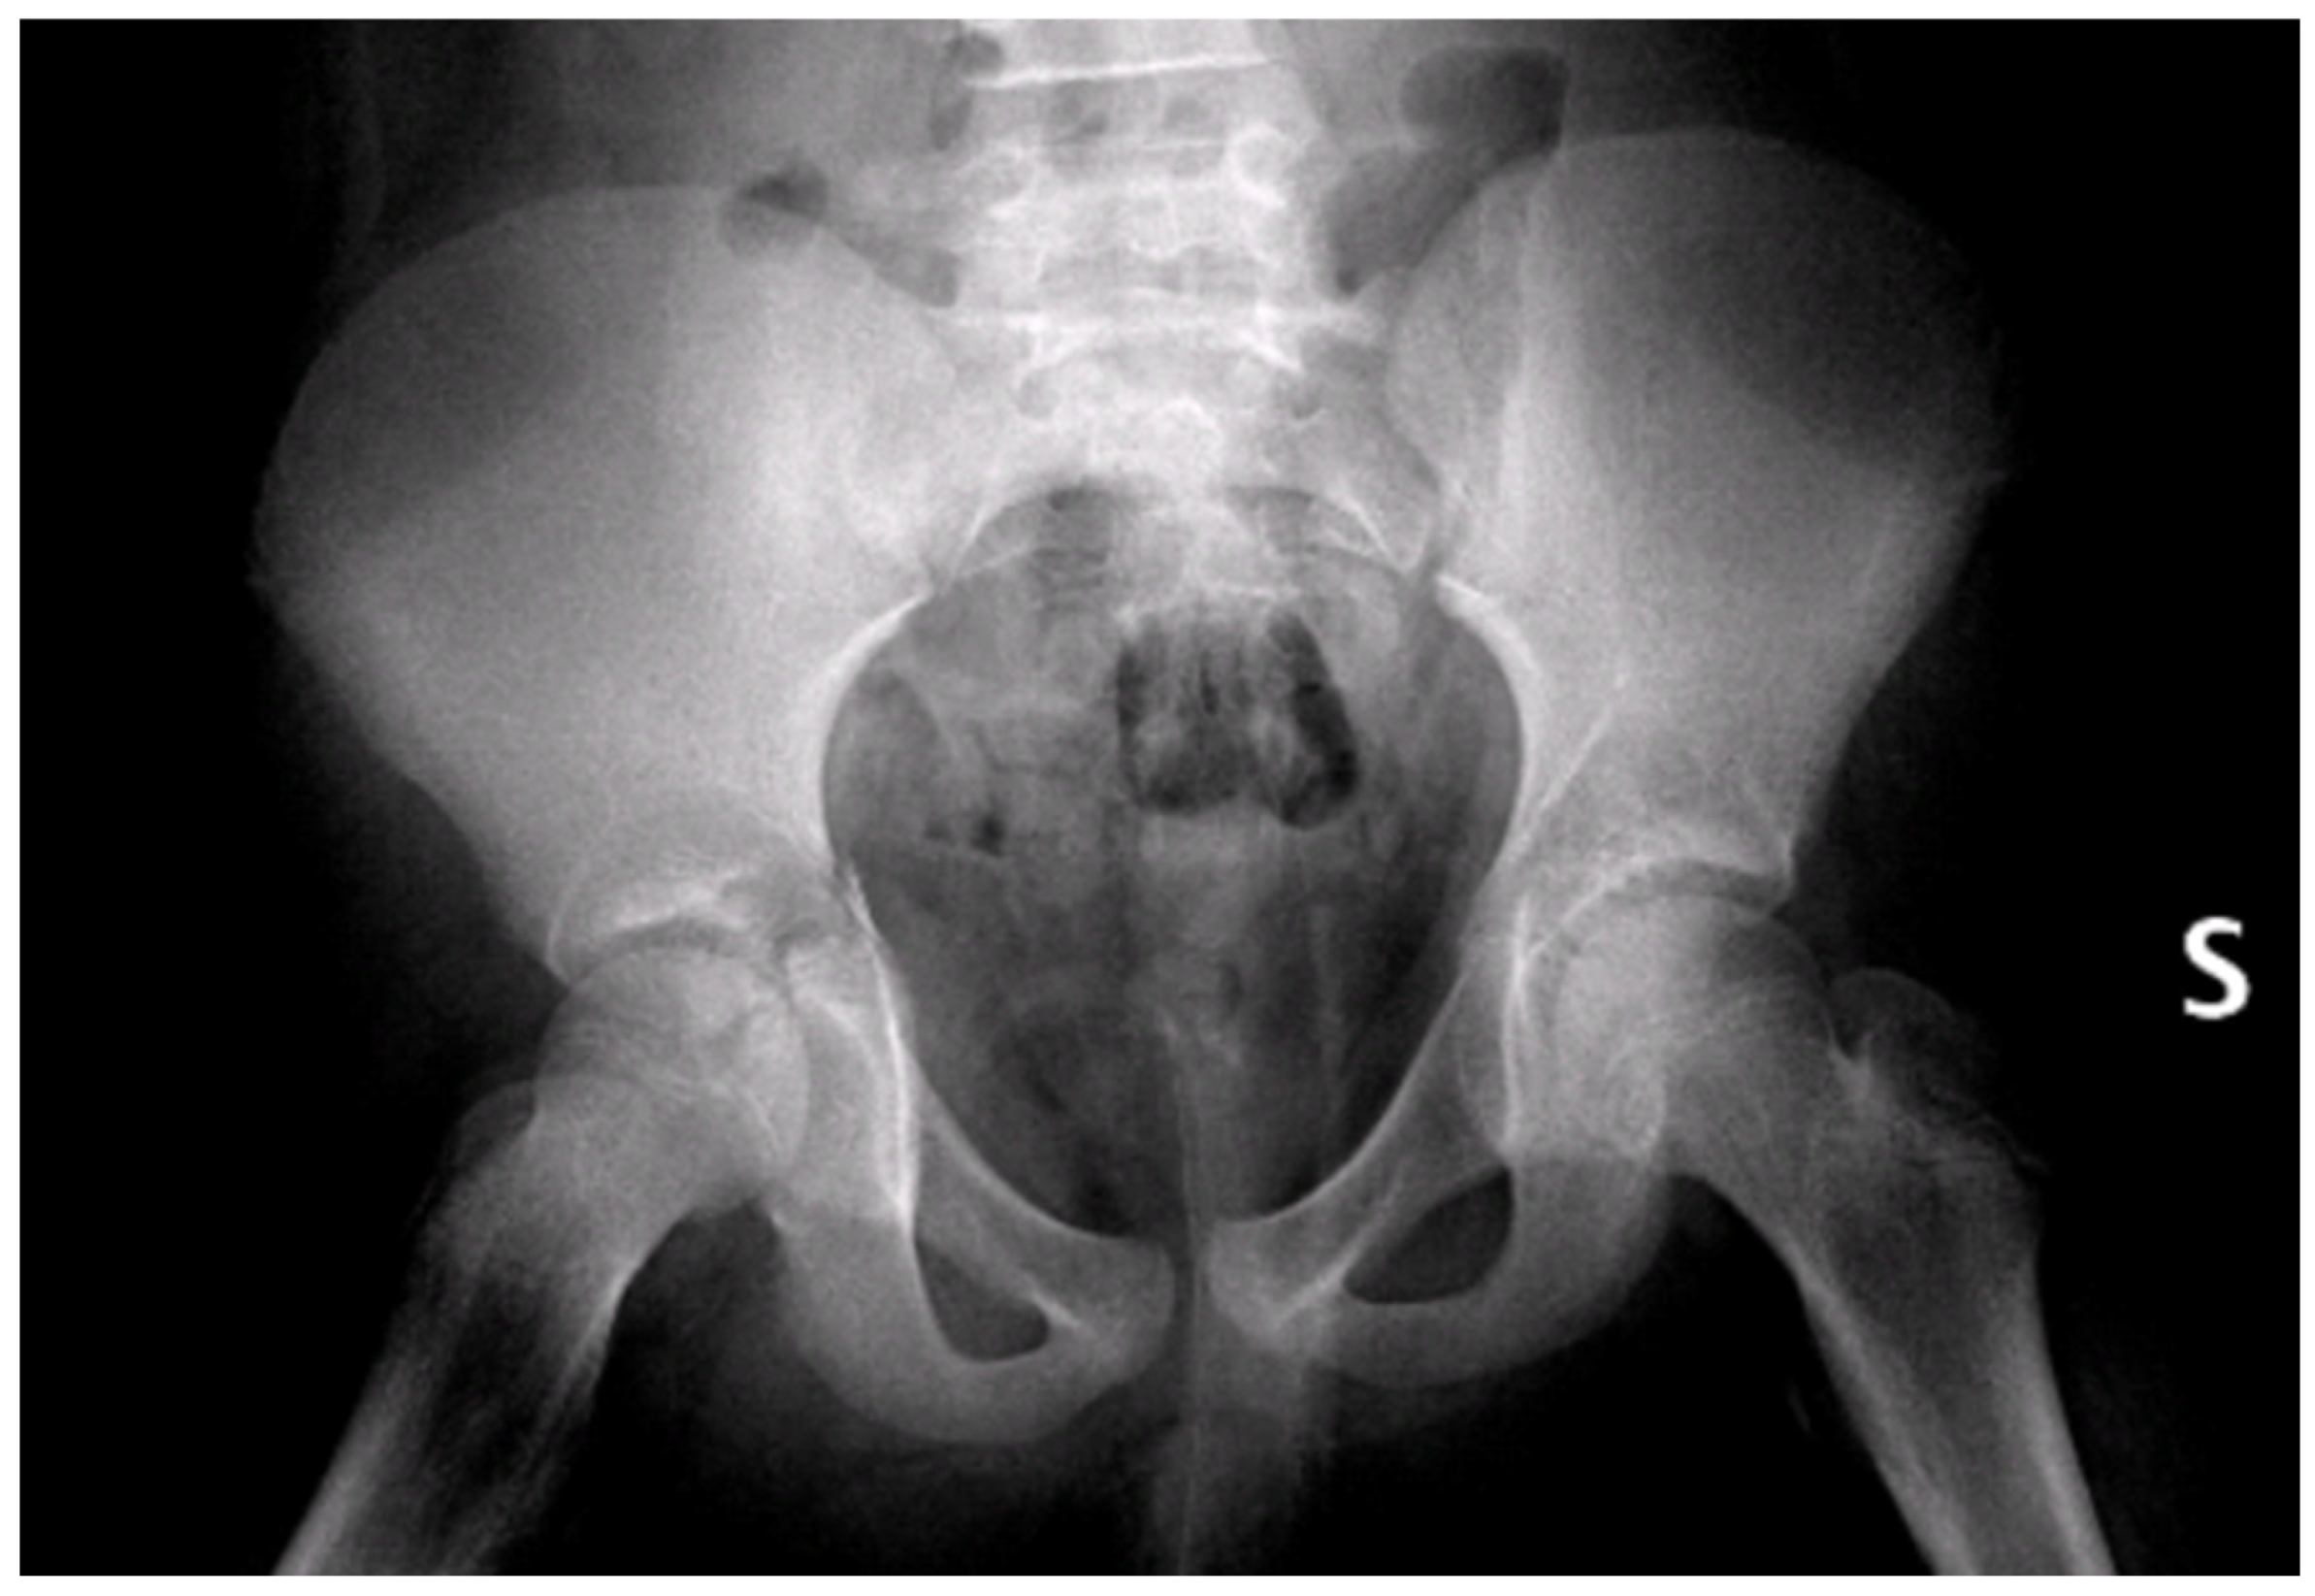

Figure 5.

CT of the pelvis showing the synthesis. (a) Axial view; (b) sagittal view; (c) coronal view. R = right; L = left; A = anterior; P = posterior.

Figure 6.

CT render of the plating area of the right acetabulum at 1 month follow-up. (a) Oblique view; (b) anteroposterior view; (c) lateral view. R = right; L = left; A = anterior; P = posterior; H = Head; F = Foot.